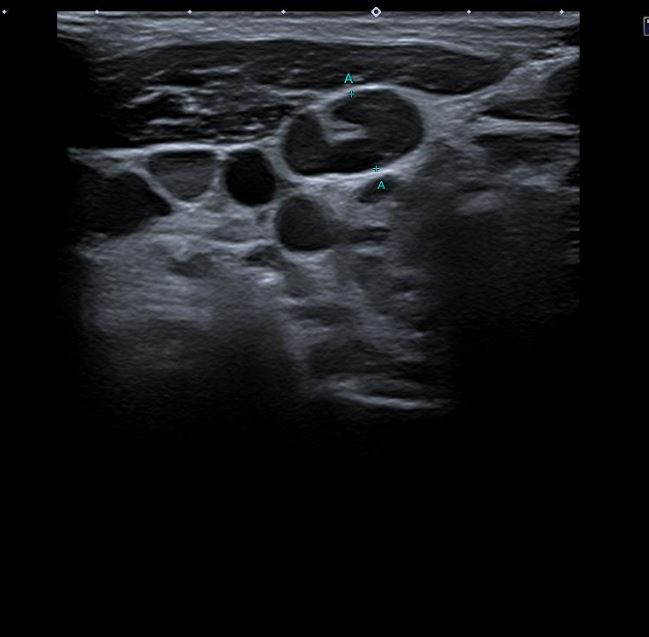

Una vez realizada la anamnesis y la exploración física, se decide realizar una ecografía clínica en la consulta, donde se objetiva un aumento difuso de tamaño del lóbulo tiroideo derecho (33,9 x 38,7 mm), levemente hipoecogénico, con áreas anecoicas en su interior y adenopatías asociadas. Se aplica Doppler color resultando positivo.